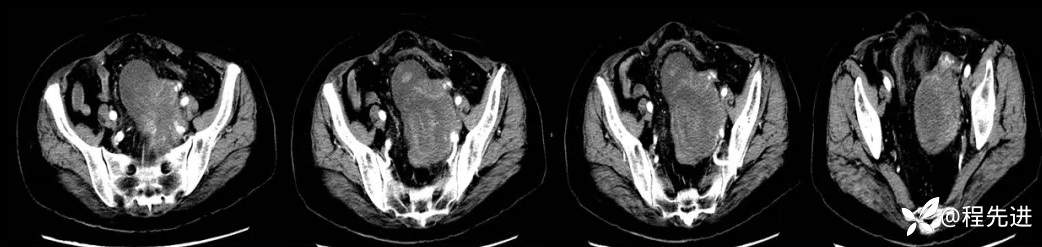

4月后患者再次腹痛半月来诊

CT平扫+增强: